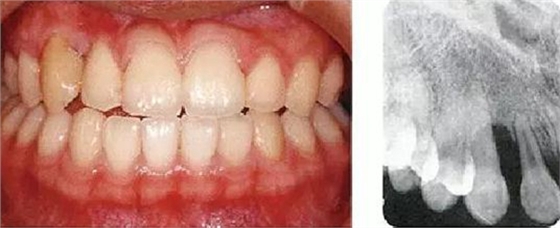

●健康且正常的牙周組織臨床圖像

●參考病例① 35歲女性

35歲女性。妊娠4個(gè)月。過去雖然接受過刷牙指導(dǎo),但菌斑控制狀態(tài)依然不理想?;颊哂邪l(fā)現(xiàn)自己刷牙時(shí)牙齦出血。

●參考病例② 25歲女性

25歲女性。菌斑控制狀態(tài)不好。齦溝除磨牙處外全在3mm以下,X光照片上左上、右下、左下的第一磨牙上有垂直性骨吸收。這個(gè)病例是參考病例①10年前的狀態(tài),是典型的侵襲性牙周炎局部型。